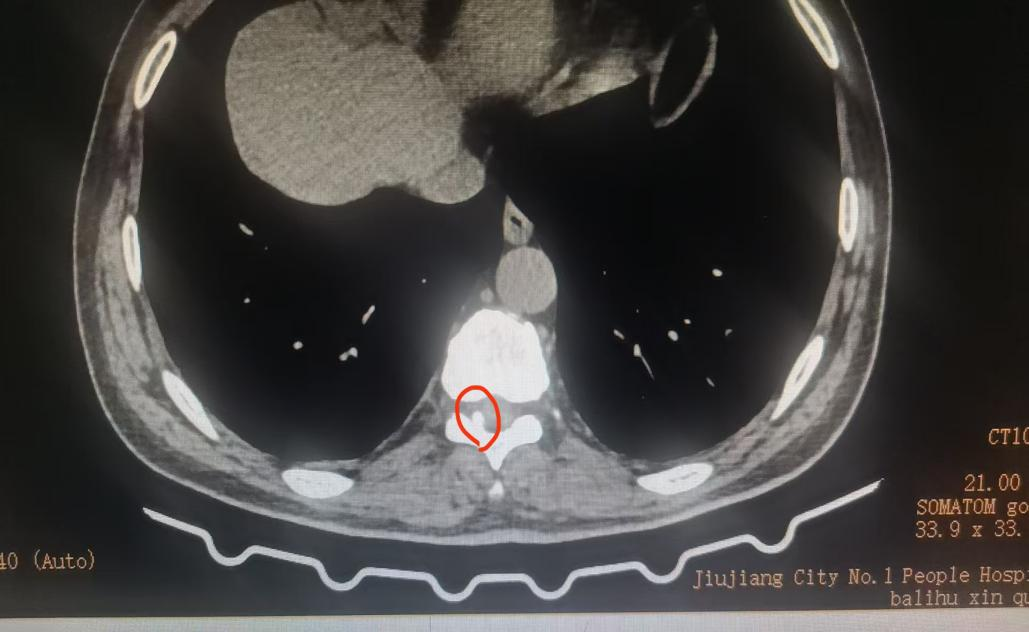

九江市第一人民医院疼痛科王晓英主任团队凭借丰富的临床专科经验,结合患者的病史、疼痛部位与性质、症状、体征,结合影像学检查精准锁定“真凶”——胸椎黄韧带骨化症。压迫脊神经根,导致相应部位疼痛及感觉异常。与董先生充分沟通后,王晓英主任团队为他实施脊柱内镜下胸椎椎管减压成形术+脊神经根粘连松解术。麻醉苏醒后的第一句话就是:“我不疼了”!董先生目前已平稳康复出院。

胸椎黄韧带骨化症(TOLF)是胸椎管内连接椎板的黄韧带发生异常骨化,这好比韧带逐渐变成了骨头,从而压迫脊髓或神经根,引发一系列症状。多发于50-70岁的中老年人、男性更为常见,亚洲人群发病率较高。常与退变、代谢异常(如糖尿病)等因素相关。